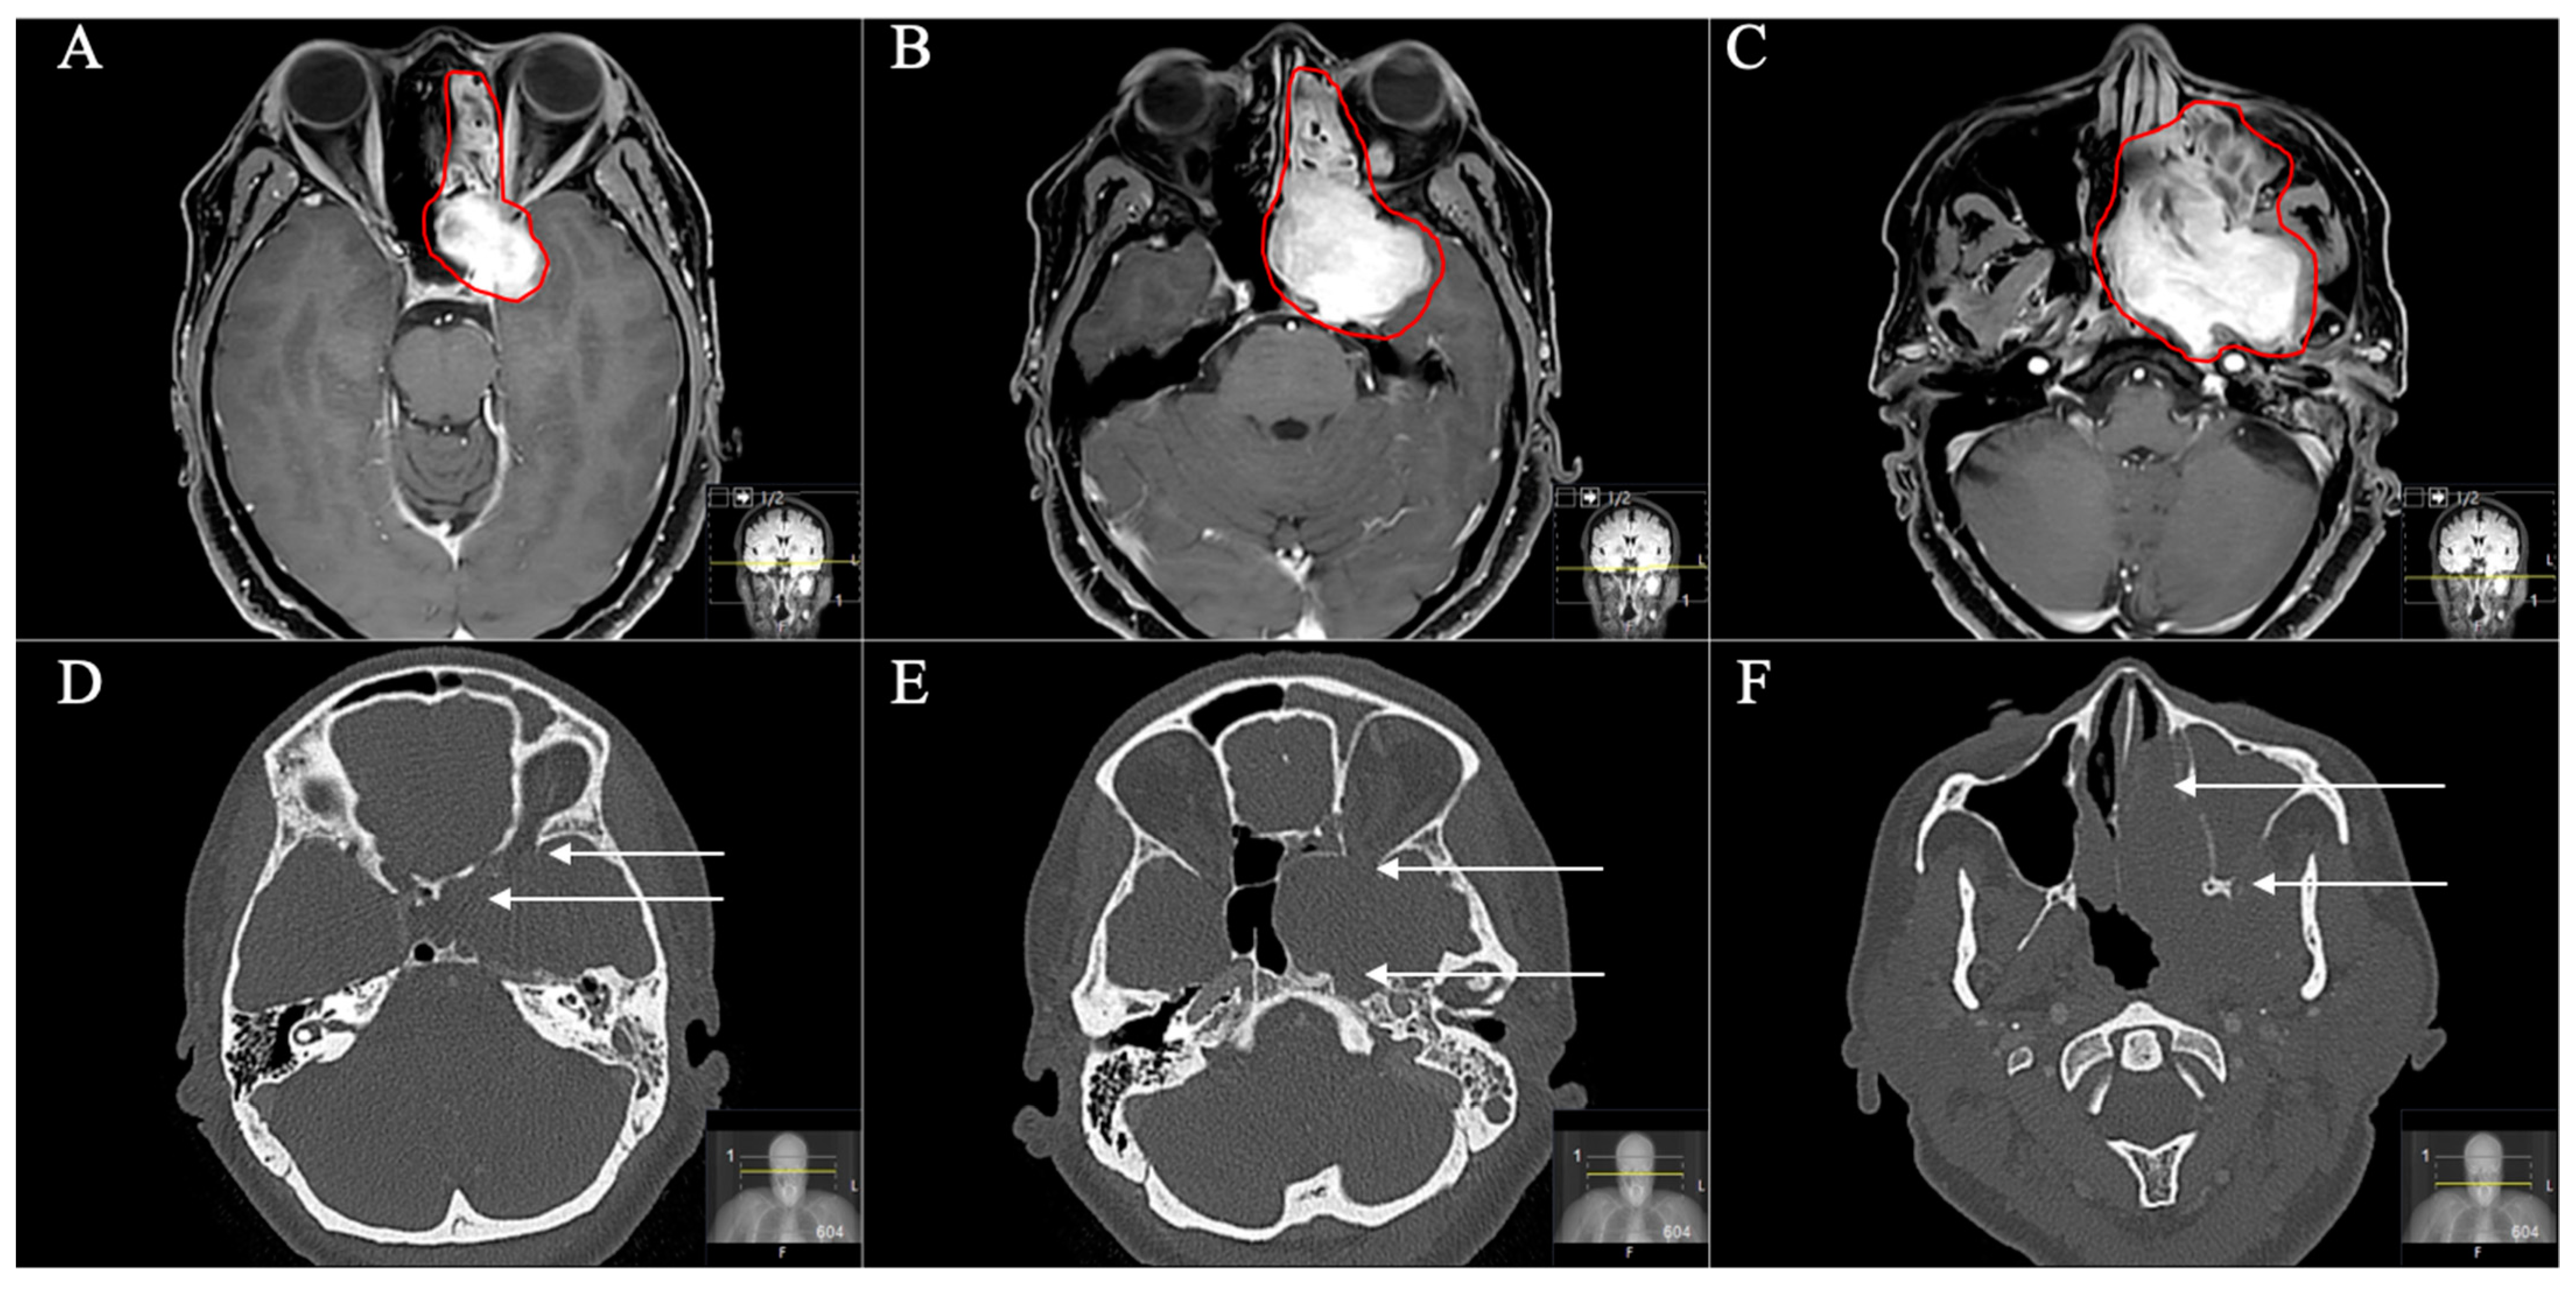

Figure 9. A 54-year-old female patient presented with slowly progressive visual impairment on the left side, trigeminal hypesthesia (V3) and an abducens nerve palsy with intermittent facial pain. (AC) Preoperative axial T1-weighted gadolinium-enhanced MRI showing a massive space-occupying mainly extracranial trigeminal schwannoma (Type D) involving the middle fossa up to the orbital funnel. The schwannoma is bounded medially by the lamina papyracea, inferiorly by the hard palate and infiltrating the pterygopalatine fossa laterally. The middle nasal concha forms the anterior border. The paranasal sinuses are completely misplaced. (DF) Preoperative axial CT scans demonstrating the destruction of the anterior skull base including the orbital funnel, the foramina ovale and rotundum and also the nasal septum and the maxillary sinus (arrows).

Figure 10. Postoperative outcome and MRI control (see Figure 9) (AC) Postoperative axial T1-weighted gadolinium-enhanced MRI showing a satisfactory STR with small remnants in the maxillary sinus (arrows in (B)). Resection was performed by an endoscopic transnasal approach using the tumor-related widened corridor to the maxillary sinus. The patient recovered very well, the visual impairment recovered subsequently, the abducens nerve palsy and the facial pain during follow-up as well. The trigeminal hypesthesia remained. The patient had follow-up controls without any progress.